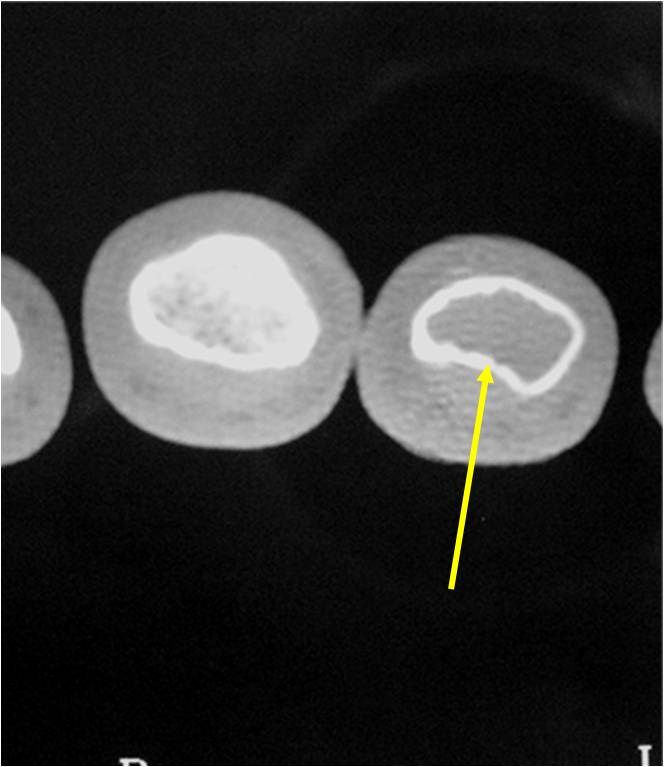

- Cortex may be scalloped and thinned in the phalanges

- Expansile remodeling with thinned cortex

- There should never be any cortical destruction nor a soft tissue component. If this exists then the tumor must be a chondrosarcoma.

- Endosteal scalloping and cortical expansion is acceptable for phalangeal tumors. In most benign long bone cartilage tumors there is minimal endosteal scalloping but there should be no cortical expansion nor thickening. There should be no cortical destruction and no soft tissue component associated with an enchondroma. Cortical destruction, periosteal thickening, cortical expansion and a soft tissue component indicates a chondrosarcoma of the long bone.

- Endosteal erosion>2/3 cortical thickness on a CT scan